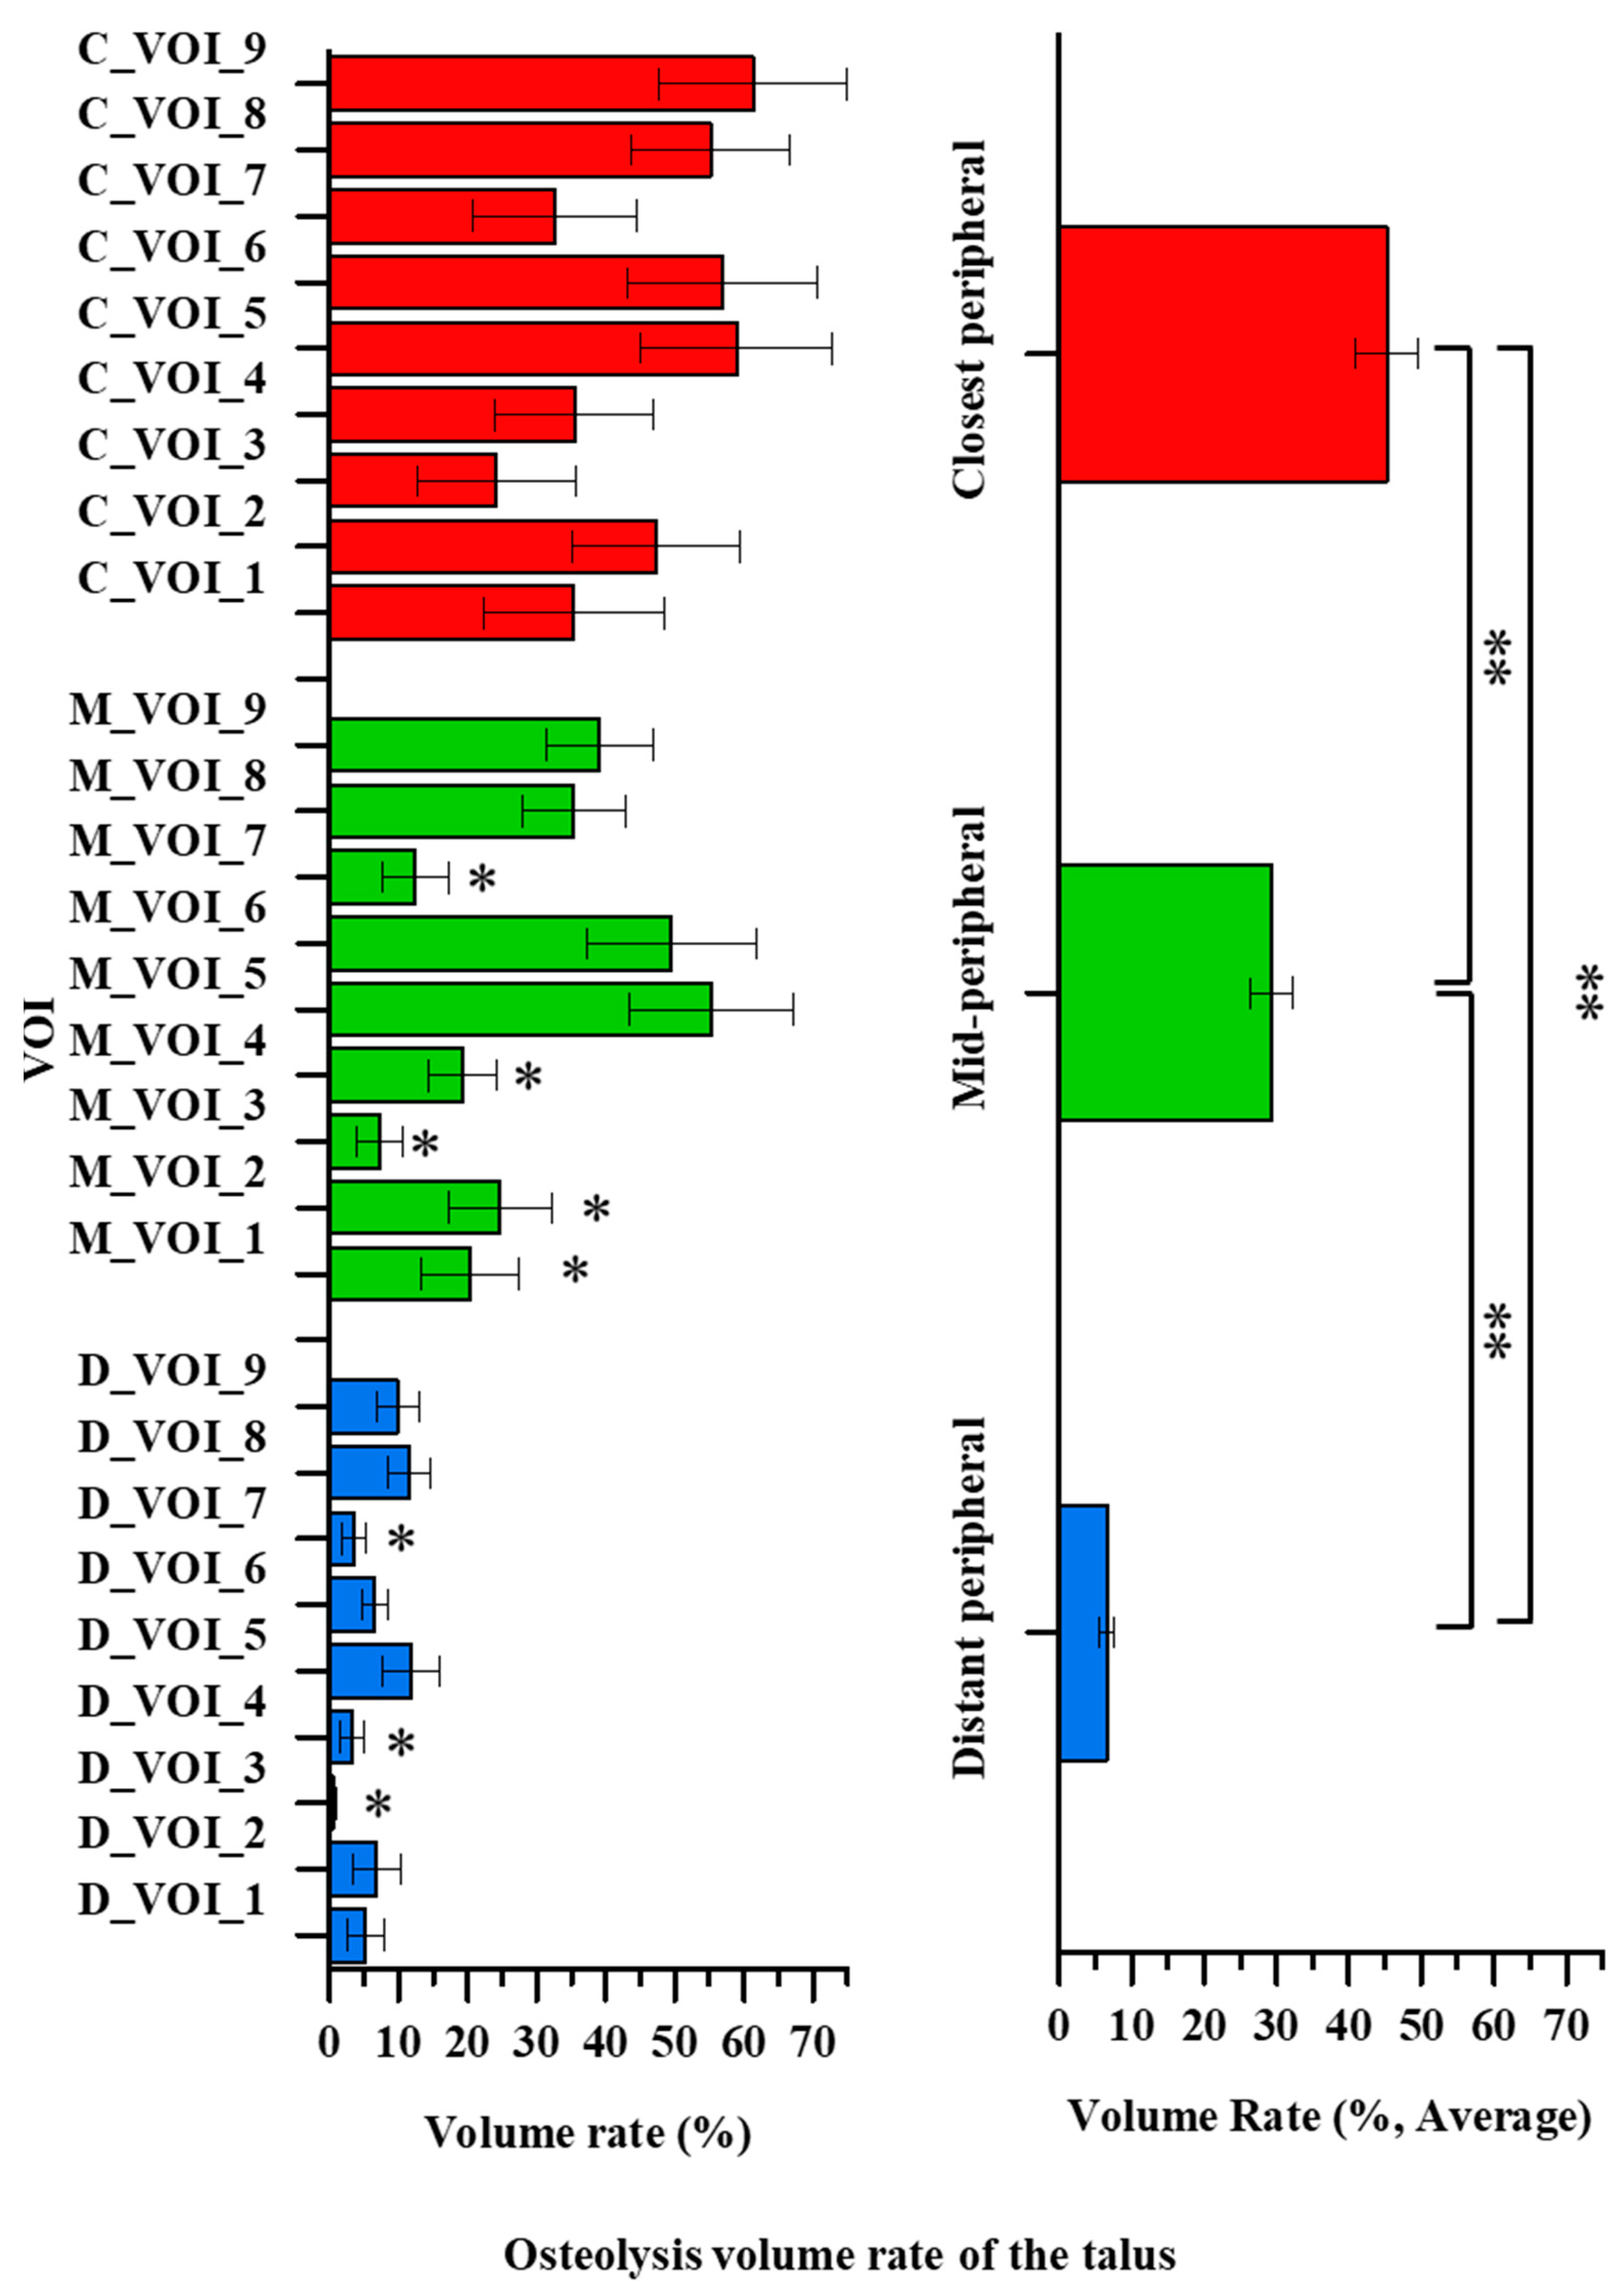

3. Results